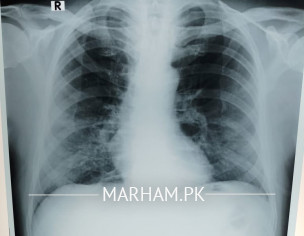

My father tested positive for corona yesterday. He has had fever 100 101, severe weakness and cough, loss of appetite etc. We got a chest extant done today and the radiologist’s report says this “â€Fibro nodulations both mid and lower zones. Rest of the lungs are clear . Cardiac size within normal limits . No evident of pleural effusion. Costophrenic angles are clear . Bony cage is intact . Conclusion. Bilateral pulmonary infection “â€. Pls advice what can be done should he be taken to the hospital?

Shortness of breath no I don’t know for sure although when he speaks he starts panting and coughing after a few sentences. He’s diabetic and hypertensive both with arthritis. This is today’s xray

Can anyone pls explain what the X-ray shows? He started antibiotic on Saturday. Azomax 500 once daily with Panadol x 2 thrice a day